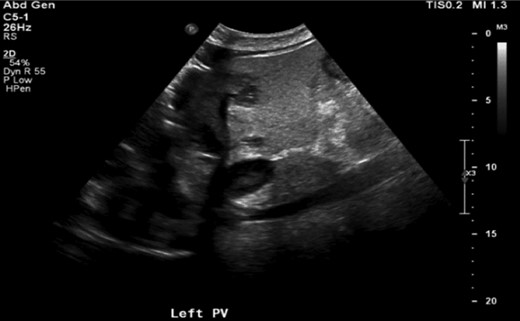

A 64-year-old Caucasian male who was treated over the course of 7 months for multiple intrahepatic abscesses, left portal vein and segmental hepatic arterial thrombosis ultimately underwent an extended left hepatectomy and was found to have XGC. The patient had a medical history significant for non-insulin dependent diabetes, chronic renal failure, chronic hepatitis C and coronary artery disease. He initially presented to the hospital seven months prior to his eventual surgery with diabetic ketoacidosis and at the time was found to have hypodense areas in the lateral and medial segments of the left lobe with extension to the hilum concerning for evolving phlegmon of the liver. Subsequent ultrasound of right upper quadrant revealed acute left portal vein thrombus (Fig. 1). The patient was started on heparin infusion and transitioned to coumadin. He was subsequently readmitted with sepsis and underwent an attempt at image-guided drainage of the liver abscess (Fig. 2) where no purulent fluid could be aspirated. A solid lesion was noted which was biopsied with final pathology noting organizing hematoma with acute and chronic inflammation.

Right upper quadrant ultrasound showing left portal vein thrombosis (arrow).